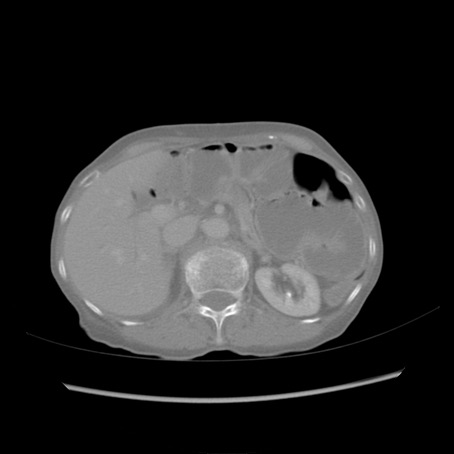

冠状断像

【症例】80歳代女性

【主訴】胸のつかえ感

【現病歴】約9時間前に食後から胸のつかえた感じあり、嘔吐あり、来院。

【既往歴】胃癌(全摘)、胆摘、虫垂炎

【身体所見】心窩部に圧痛あり、反跳痛なし。

【データ】WBC 5700、CRP 0.05